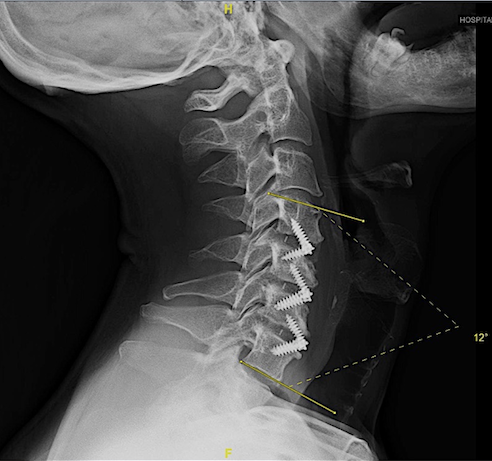

En mi opinión, las cajas intersomáticas atornilladas (CISA) son la mejor opción para corregir la cifosis cervical anterior, especialmente en patología multinivel. Además, a diferencia de «Cage Stand Alone» o caja cervical + placa; la lordosis conseguida se mantiene mejor en el tiempo.

En la técnica quirúrgica es clave asegurar una descompresión adecuada y respetar al máximo la anatomía de los platillos cervicales lo que, en algunos casos de espondilosis avanzada, es laborioso.

Aquí presento dos ejemplos.